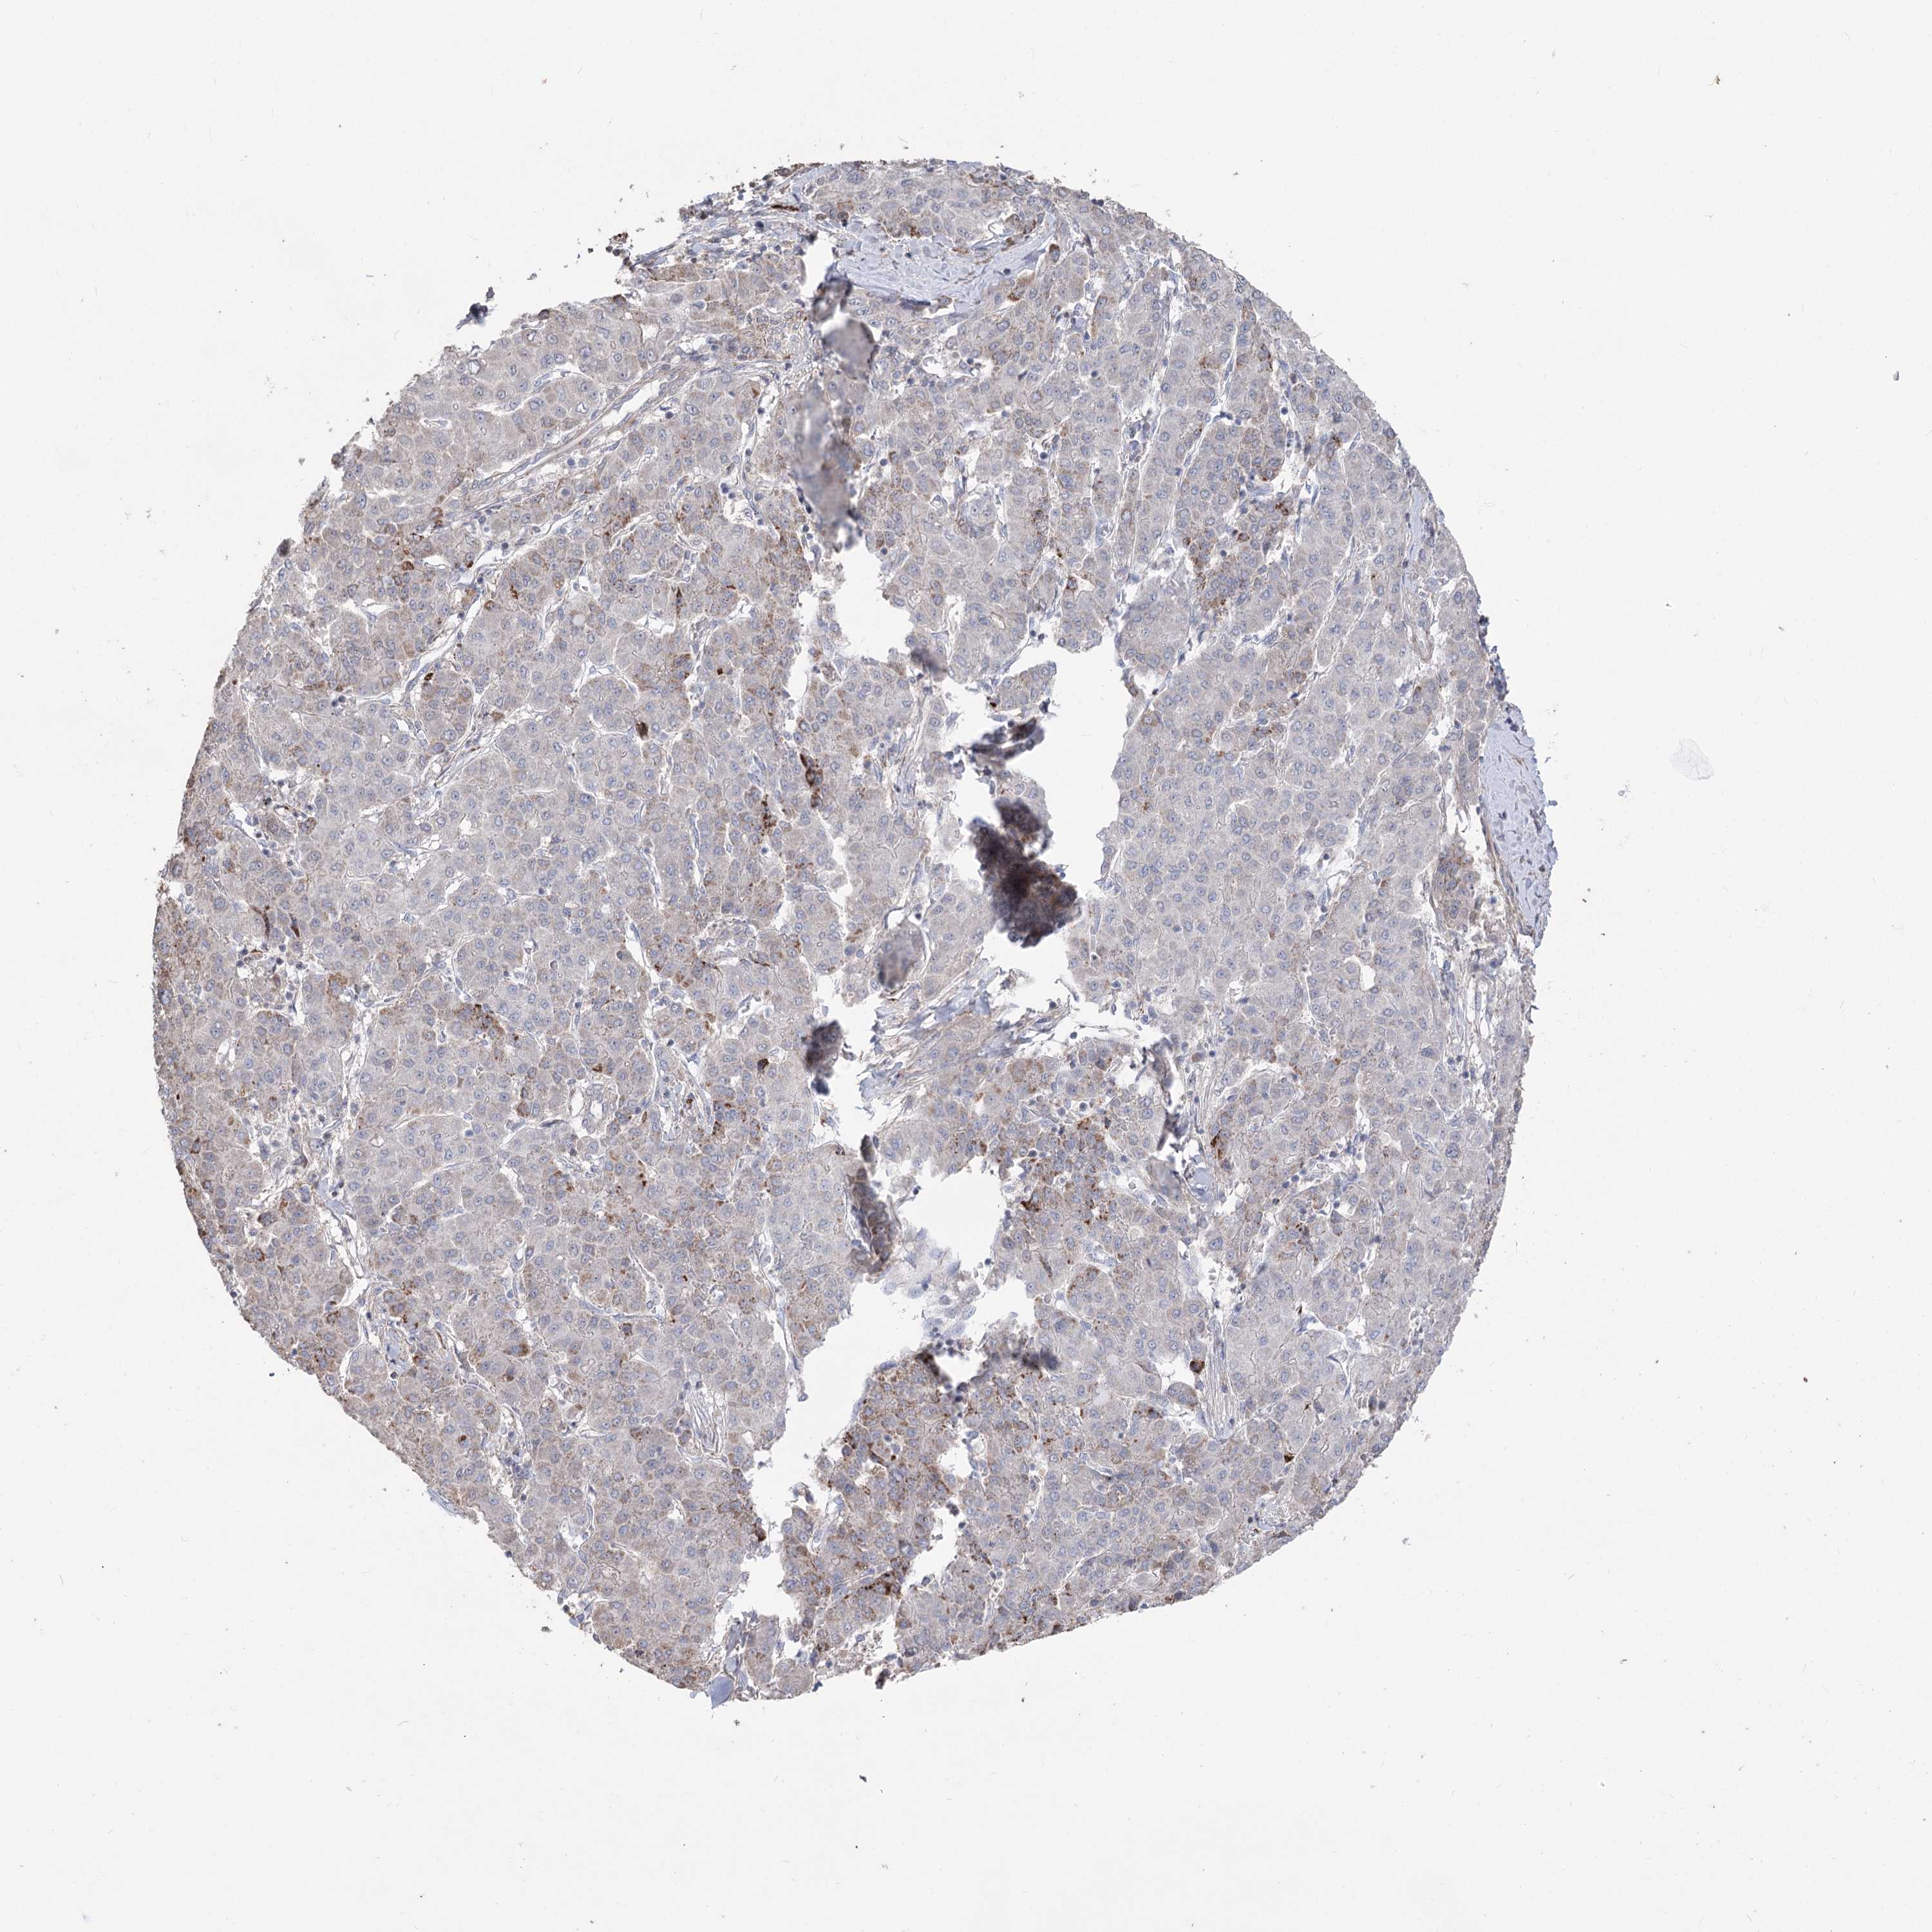

LIVER CANCER - Protein expressioni

A mouse-over function shows sample information and annotation data. Click on an image to view it in a full screen mode. Samples can be filtered based on level of antibody staining by selecting one or several of the following categories: high, medium, low and not detected. The assay and annotation is described here.

Note that samples used for immunohistochemistry by the Human Protein Atlas do not correspond to samples in the TCGA dataset.

Antibody stainingi

Antibody staining in the annotated cell types in the current human tissue is reported as not detected, low, medium, or high, based on conventional immunohistochemistry profiling in selected tissues. This score is based on the combination of the staining intensity and fraction of stained cells.

Each image is clickable and will lead to virtual microscopy that enables deeper exploration of all samples and also displays staining intensity scores, fraction scores and subcellular localization as well as patient and tissue information for each sample.

Antibody HPA035959

Antibody HPA035960

Staining

High

Medium

Low

Not detected

Intensity

Strong

Moderate

Weak

Negative

Quantity

>75%

75%-25%

<25%

None

Location

Nuclear

Cytoplasmic/membranous

Cytoplasmic/membranous,nuclear

Cholangiocarcinoma

Carcinoma, Hepatocellular, NOS